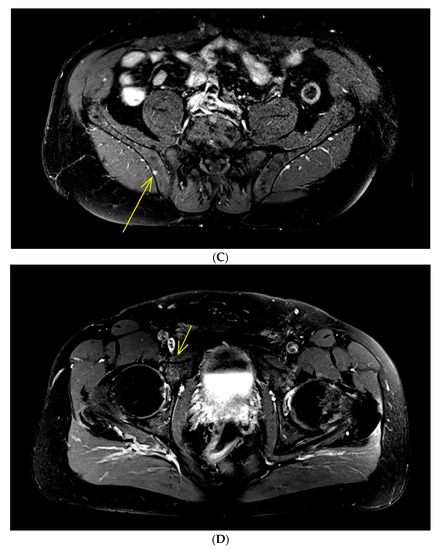

FDG-PET/CT imaging has also proved its utility in SMM setting, showing prognostic value. Even if the latest updated MM IMWG definitions [3] indicated that osteolysis on CT was mandatory when an FL is depicted by FDG-PET/CT for considering it as a criterion for starting therapy at MM initial diagnosis, all prospective studies since 2009 defined FL as foci of uptake with or without osteolysis because metabolic could precede morphological abnormalities (Figure 2).

Figure 2.

IgAk SMM patient with only one focal lesion of a thoracic vertebral body (maximum standardized uptake value (SUVmax): 15.34) depicted in FDG-PET/CT. (A: Positron emission tomography (PET) slice and B: PET/CT fused slice). Because of the absence of osteolytic lesions on the opposite CT (C), biopsy was performed in this area, revealing a focal monotype k accumulation of clonal plasma cells, upgrading the patient to symptomatic multiple myeloma (MM) requiring treatment.

In SMM, a positive FDG-PET/CT defined by the presence of FL without underlying osteolytic lesions is associated with a rapid progression to symptomatic MM. Indeed, in a cohort of 122 SMM patients assessed by FDG-PET/CT, the probability of progression to symptomatic MM without therapy within 2 years for positive FDG-PET/CT patients was 75% versus 30% for patients with a negative PET [15]. It should be clarified that of 25 patients with a positive FDG-PET/CT, the probability of progression was 87% at 2 years in those with evidence of underlying osteolysis (n = 16) and 61% in patients without evidence of osteolysis (n = 9). In another prospective study of 120 SMM patients, the Bologna Group [16] reported a similar rate of progression to symptomatic MM at 2 years of 58% for patients with positive PET (all without evidence of underlying osteolysis) versus 33% for patients with a negative PET. These FDG-PET/CT results have been published after the latest IMWG MM updated definitions [3] and thus are not yet considered as an MDE leading to the recommendation to treat these patients.